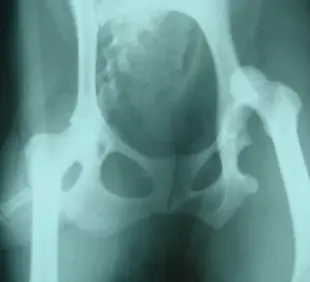

• 股関節脱臼

• 股関節形成不全

整形外科